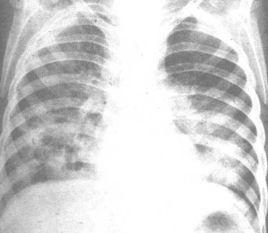

3、監護 在嚴重肺部疾病患者誤吸後的初始階段,病情可能相對穩定,醫師切不可松警惕,應密切觀察數小時。常規監護包括呼吸頻率、血壓、脈率、尿量和體溫。定期檢測動脈血氣並計算P(A-a)O2。儘管X 線胸片在最初數小時可能正常。但胸片檢查須常規進行。定期進行深部呼吸道分泌物的細菌革蘭染色和培養(每24~48h 1 次)。